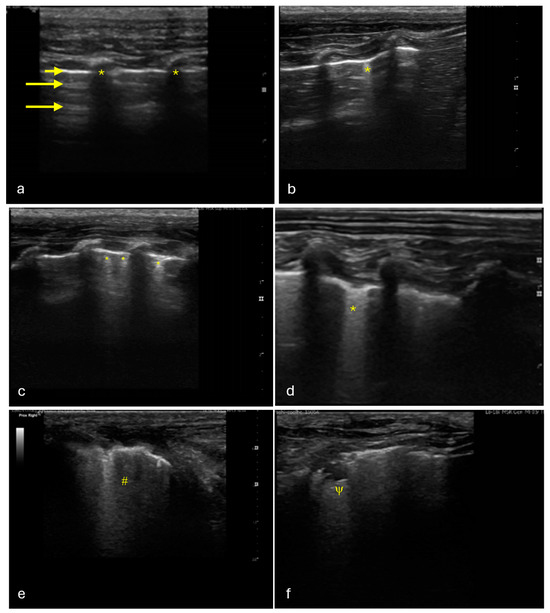

4.2. Thoracic LUS